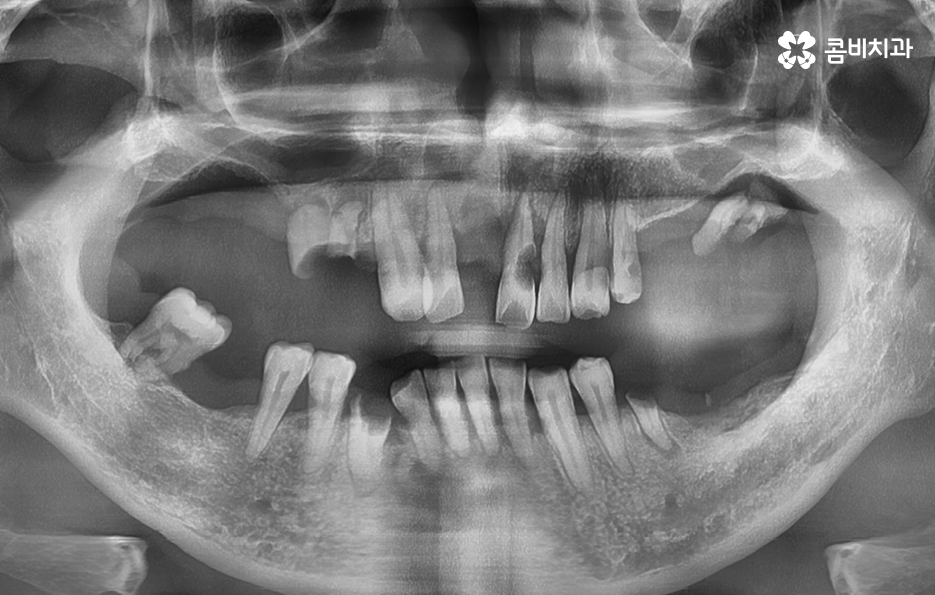

위 환자분의 엑스레이 사진을 보면 치아의 뿌리 부분에 가깝게 잇몸이 내려앉은 것을 볼 수 있는데 치아의 구조에서 뿌리쪽은 법랑질이 없기 때문에 잇몸이 내려앉고 잇몸 뼈가 치주염으로 녹게 되면 치아가 너무 아파서 식사를 하기에도 어렵고 물 한잔만 마셔도 이가 시릴 정도로 일상에 지장을 느끼실 수 있어요

결국 치아가 흔들릴 정도까지 잇몸 뼈가 녹고 치아의 뿌리도 함께 손상된다면 발치로 이어지겠지만 임플란트의 과정은 잇몸이 건강하신 환자분들과 잇몸이 약해지고 얇아지신 분들의 경우에는 치료적인 접근이 달라지기 마련인데 일반적인 임플란트의 경우 치아를 발치하고 임플란트를 올리기 까지 약 5~6개월 정도가 소요된다면 잇몸 뼈가 녹을 정도로 잇몸이 약해진 분들의 경우에는 뼈이식을 포함하여 경우에 따라서는 1년까지도 치료 기간이 걸릴 수 있기 때문에 임플란트 치료 역시도 어려운 과정을 겪게 될 수 있다는 점에서 치주염 발치의 경우 결코 가볍지 않은 시술 과정이 동반될 수 있어요